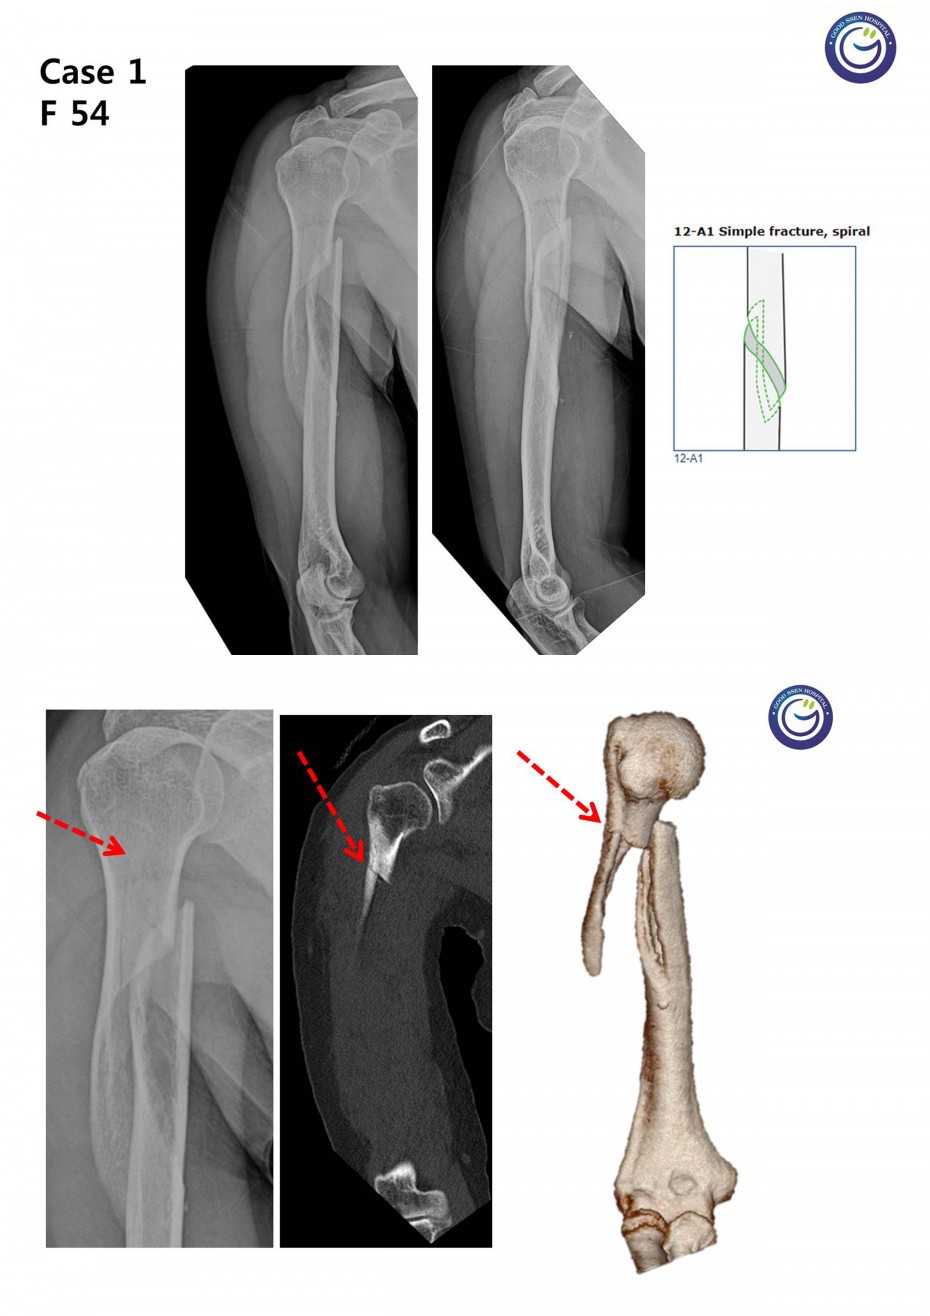

관절을 침범하는 심한 분쇄골절

절개없이 고정하는 최소침습적 고정방법 (MIPO)